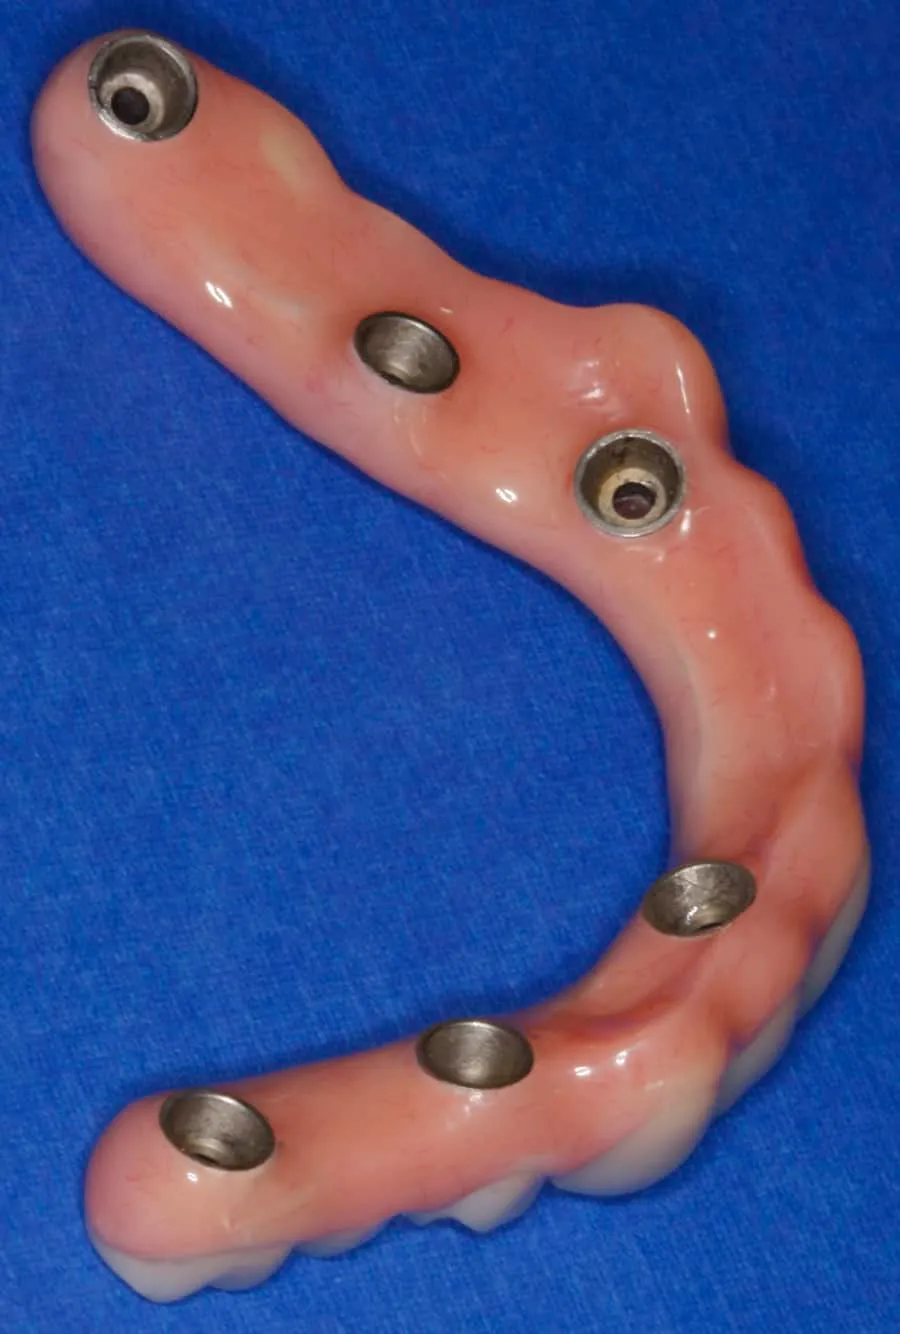

Fixed; Full Arch Restoration; Acrylic-fused-to-Metal; Fixed Partial Denture; Implant Supported and Implant Retained

After: Maxillary (upper), acrylic fused to metal, fixed (hybrid) screw-retained (retrievable) restoration supported by 6 titanium root form dental implants. The restoration is fixed, therefore only Dr. Leopardi can remove it for routine maintenance and hygiene, as needed. The patient cleans the fixed restoration as he does his natural lower teeth, with a tooth-brush, floss and water-pick. The outcome is improved function, mastication/diet, aesthetics and quality of life.